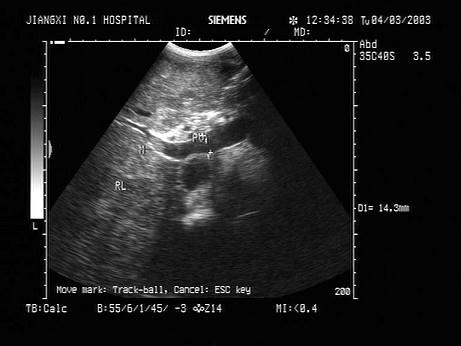

问题 患者体检发现肝脏体积增大,超声见右叶巨大的强回声光团,边界见声晕,门脉见实质性光团充填,如图所示,考虑为?(?)

选项 A.肝癌并门脉癌栓 B.肝脓肿 C.肝囊肿 D.肝结核 E.肝血管瘤

答案 A